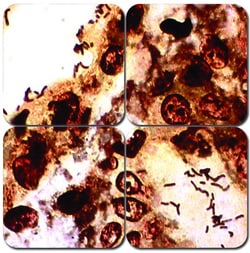

CHROMagar™chromogenic plates are easy to prepare - just add water to the dehydrated media, bring to a boil, let it cool down and pour! Use the entire pack, or if there is a need for a smaller number of plates, just a portion. CHROMagar™ products are sold in dehydrated form. DRG offers the 5L size (after reconstitution). If kept under appropriate storage temperatures, CHROMagar™ powder products have a long shelf life (2-3 years). This flexibility is essential to avoid the costly waste resulting from unused plates. This product comes with the refrigerated supplement SU620; these are shipped free of charge along with the product. Supplements contain compounds that cannot be heated, therefore the compounds would degrade in the base if stored together for a long time.